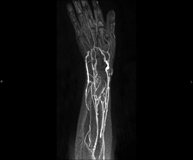

Soft tissue lesion MRI angiography

A non-invasive diagnostic test that involves studying the vascularisation of any soft tissue lesion (skin, muscle, tendon, etc.) by obtaining high-definition anatomical images using an electromagnetic field and radio waves (with transmitter and receiver). The use of paramagnetic intravenous contrast (gadolinium) is essential. However, it is a radiation-free procedure. The quality of the images allows for 2D and 3D reconstructions. It is particularly suitable as a pre-surgical vascular map in patients with muscle, skin, subcutaneous, etc. injuries.